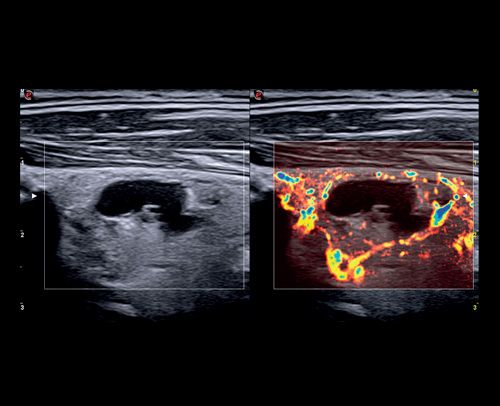

- Ecografia dell'addome completo, Ecografia dell'addome superiore o inferiore, Ecografia ed Eco-Color-Doppler della tiroide, Ecografia dei linfonodi / delle stazioni linfonodali (collo, ascelle, inguine, altri distretti), Ecografia prostatica, Ecografia dei reni e surreni, Ecografia testicolare (varicocele), Ecografia dei tessuti molli (studio lesioni cutanee, cisti, etc..), Ecografia articolare, Ecografia muscolo-scheletrica.

- Eco-Color-Doppler (ECD) dei tronchi sovra-aortici (TSA), ECD dell'aorta addominale e dei vasi iliaci, ECD aorto-iliaco, ECD celiaco-mesenterico, ECD degli arti inferiori arterioso o venoso, ECD degli arti superiori arterioso o venoso, ECD testicolare, ECD delle arterie temporali, ECD trans-cranico senza mdc.